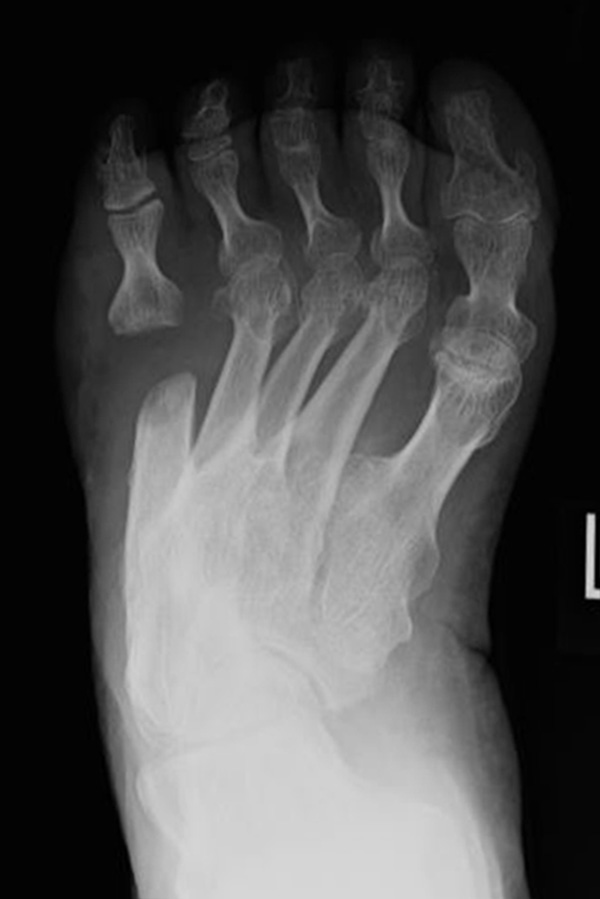

Abb. 3a, b: Präoperatives (a) und postoperatives (b) Röntgenbild bei Korrektur einer Typ I Deformität durch eine Exostosenabtragung.